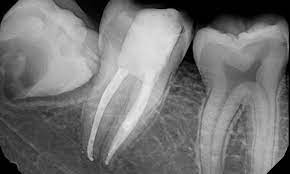

Root Canal Treatment (RCT) is a dental procedure to treat infections or damage within a tooth’s pulp, which contains nerves and blood vessels. The process involves removing the infected or damaged pulp, cleaning the canal, and sealing it to prevent further infection. After cleaning, the tooth is often restored with a crown to ensure strength and functionality. RCT alleviates pain, preserves the natural tooth, and prevents the spread of infection. While notorious for being associated with discomfort, modern techniques and anesthesia make root canal treatments relatively painless, providing an essential option to save a tooth and maintain oral health. Regular follow-ups ensure long-term success.

- Pulp removal and cleaning: Infected or damaged pulp is removed, and the root canals are thoroughly cleaned and disinfected.

- Filling and restoration: The cleaned canals are filled with a sealing material, and a temporary filling or crown is placed initially, followed by a permanent restoration to protect and strengthen the treated tooth.